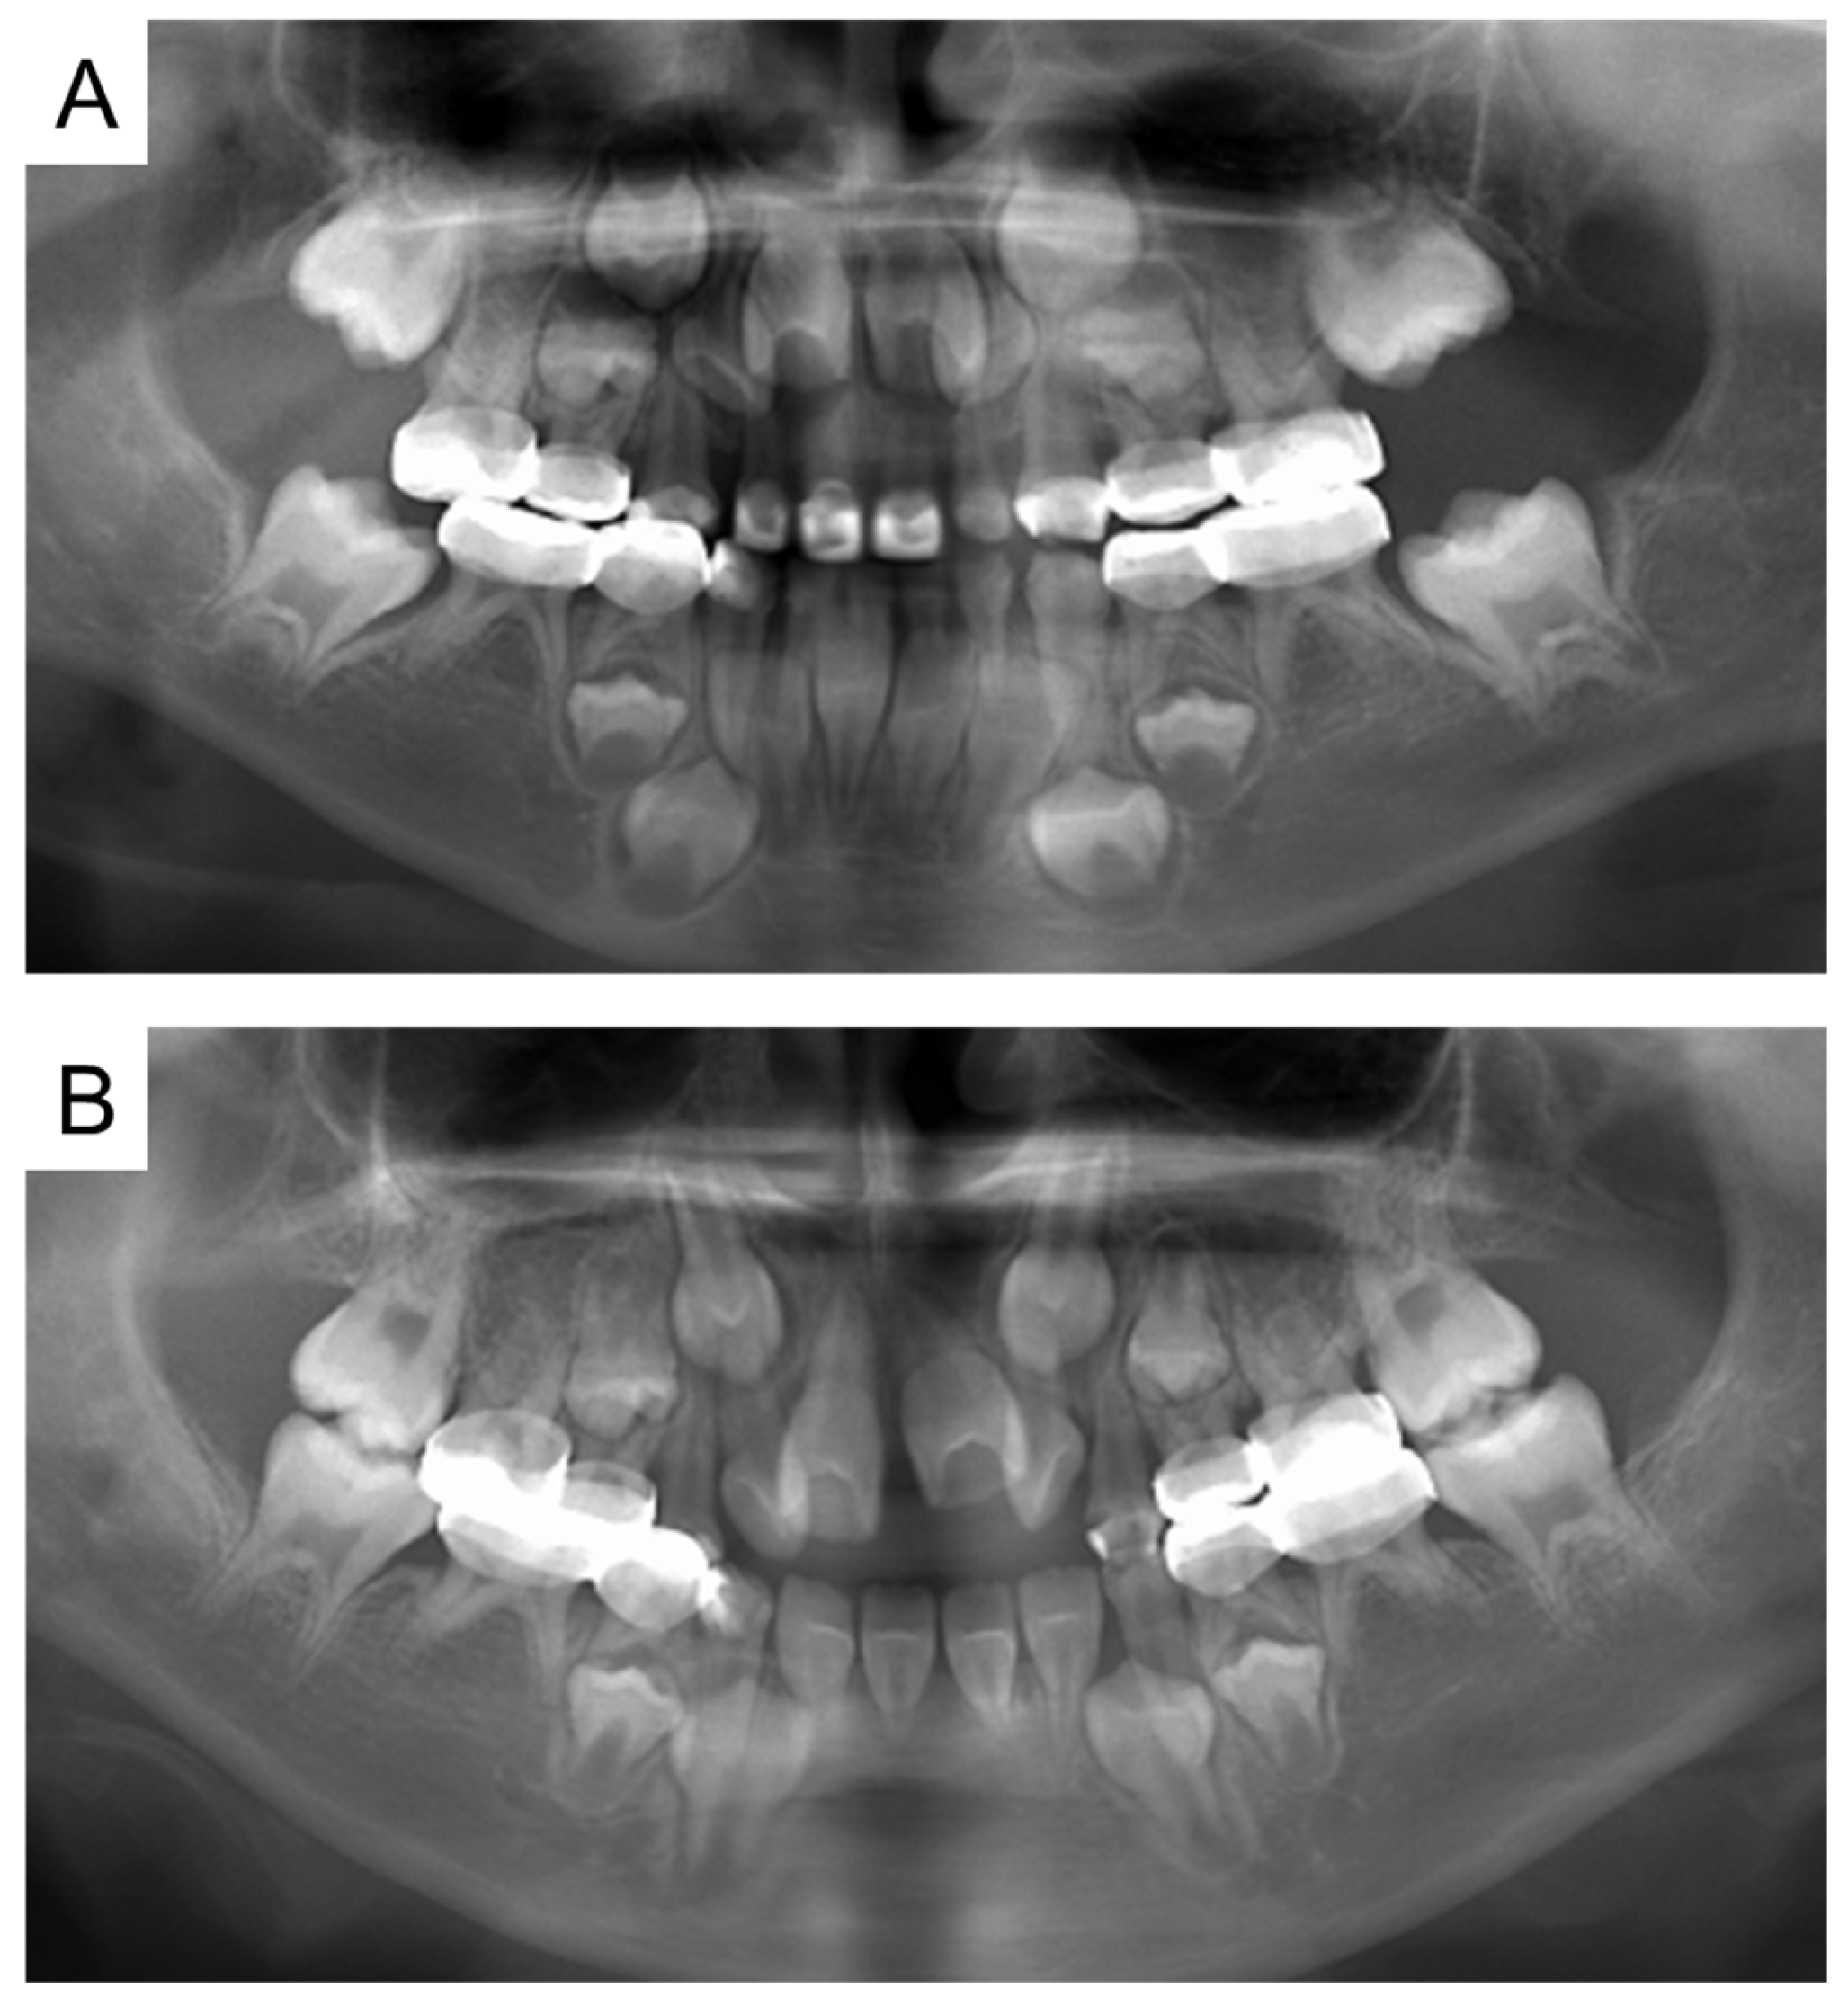

| Tooth | Diagnosis | Final Restoration |

|---|---|---|

| Maxilla | ||

| 51 | C2 | Resin-based composite crown |

| 52 | C2 | Resin-based composite crown |

| 53 | C2 | Resin filling |

| 54 | C2 | Preformed stainless-steel crown |

| 55 | C2 | Preformed stainless-steel crown |

| 61 | C2 | Resin-based composite crown |

| 62 | C2 | Resin-based composite crown |

| 63 | C2 | Resin filling |

| 64 | C2 | Preformed stainless-steel crown |

| 65 | C2 | Preformed stainless-steel crown |

| Mandible | ||

| 71 | C2 | No treatment |

| 72 | C2 | Resin filling |

| 73 | C2 | Resin filling |

| 74 | C2 | Preformed stainless-steel crown |

| 75 | C2 | Preformed stainless-steel crown |

| 81 | C2 | No treatment |

| 82 | C2 | Resin filling |

| 83 | C2 | Resin filling |

| 84 | C2 | Preformed stainless-steel crown |

| 85 | C2 | Preformed stainless-steel crown |